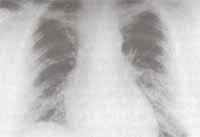

Figura No 2. Acercamiento de la imagen anterior donde se aprecia opacidad cavitada con mayor detalle.

Se inició tratamiento con líquidos, corrección de electrolitos y fluconazol. En las primeras 24 horas cursó con hipotensión refractaria a la administración de volumen, distensión abdominal, dificultad respiratoria severa con hemoptisis e hipoxemia. La radiografía de tórax mostró infiltrados alveolares difusos y bilaterales (Figura No. 4).

Figura No 4. Radiografía de tórax simple que muestra imagen sugestiva de edema pulmonar.